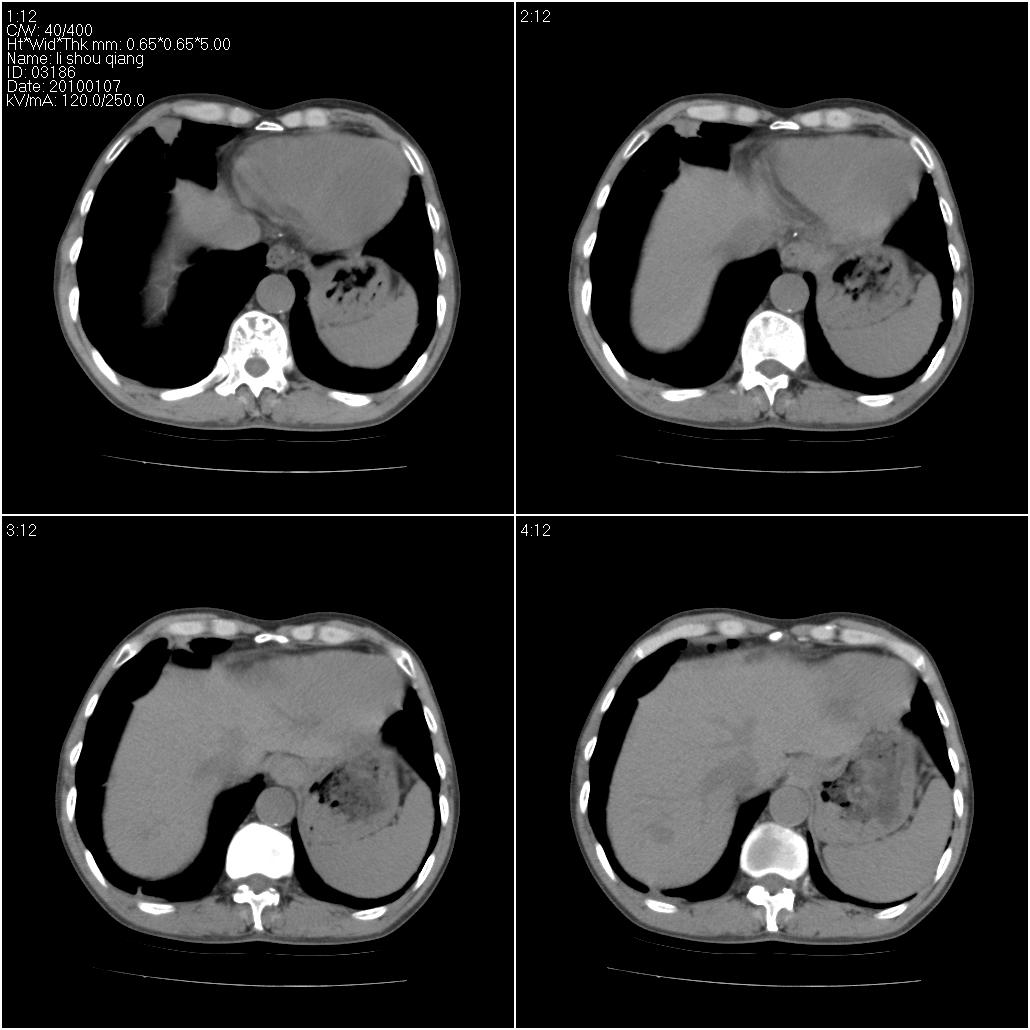

3、建议增强除外主动脉弓息室样动脉瘤。

右肺中叶外侧段可见团块影,外形不规则,内见空泡征。左下肺见蜂窝状低密度透亮影,部分层面主动脉旁瘤样突出。考虑右肺中叶外围型肺癌可能性大,左下肺支气管扩张,主动脉弓瘤样突出。

考虑右肺癌可能性大,左下肺支气管扩张,主动脉弓瘤样突出?建议增强

3、建议冠状位重建除外主动脉弓息室样动脉瘤。